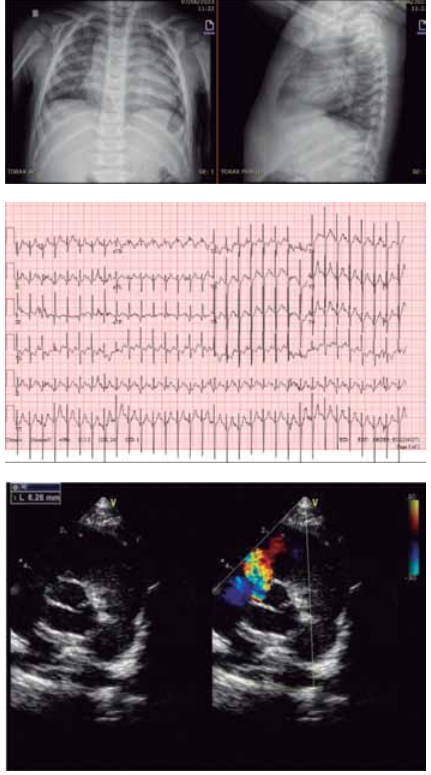

Paciente de 1 ano e 1 mês veio encaminhada, via CROSS, por cardiopatia congênita. A avó refere que a criança, desde os 2 meses de idade, fica com a boca roxa quando chora. Lembra de ter levado a uma UPA, sendo auscultado um sopro na ocasião e aferida saturação periférica de oxigênio em ar ambiente de 98%. Avó refere, também, sudorese importante e cansaço às mamadas com dificuldade de ganho pondo-estatural, além de infecções respiratórias frequentes.

(Arquivo pessoal; imagens usadas com autorização)

Diante do exposto, o diagnóstico correto é: